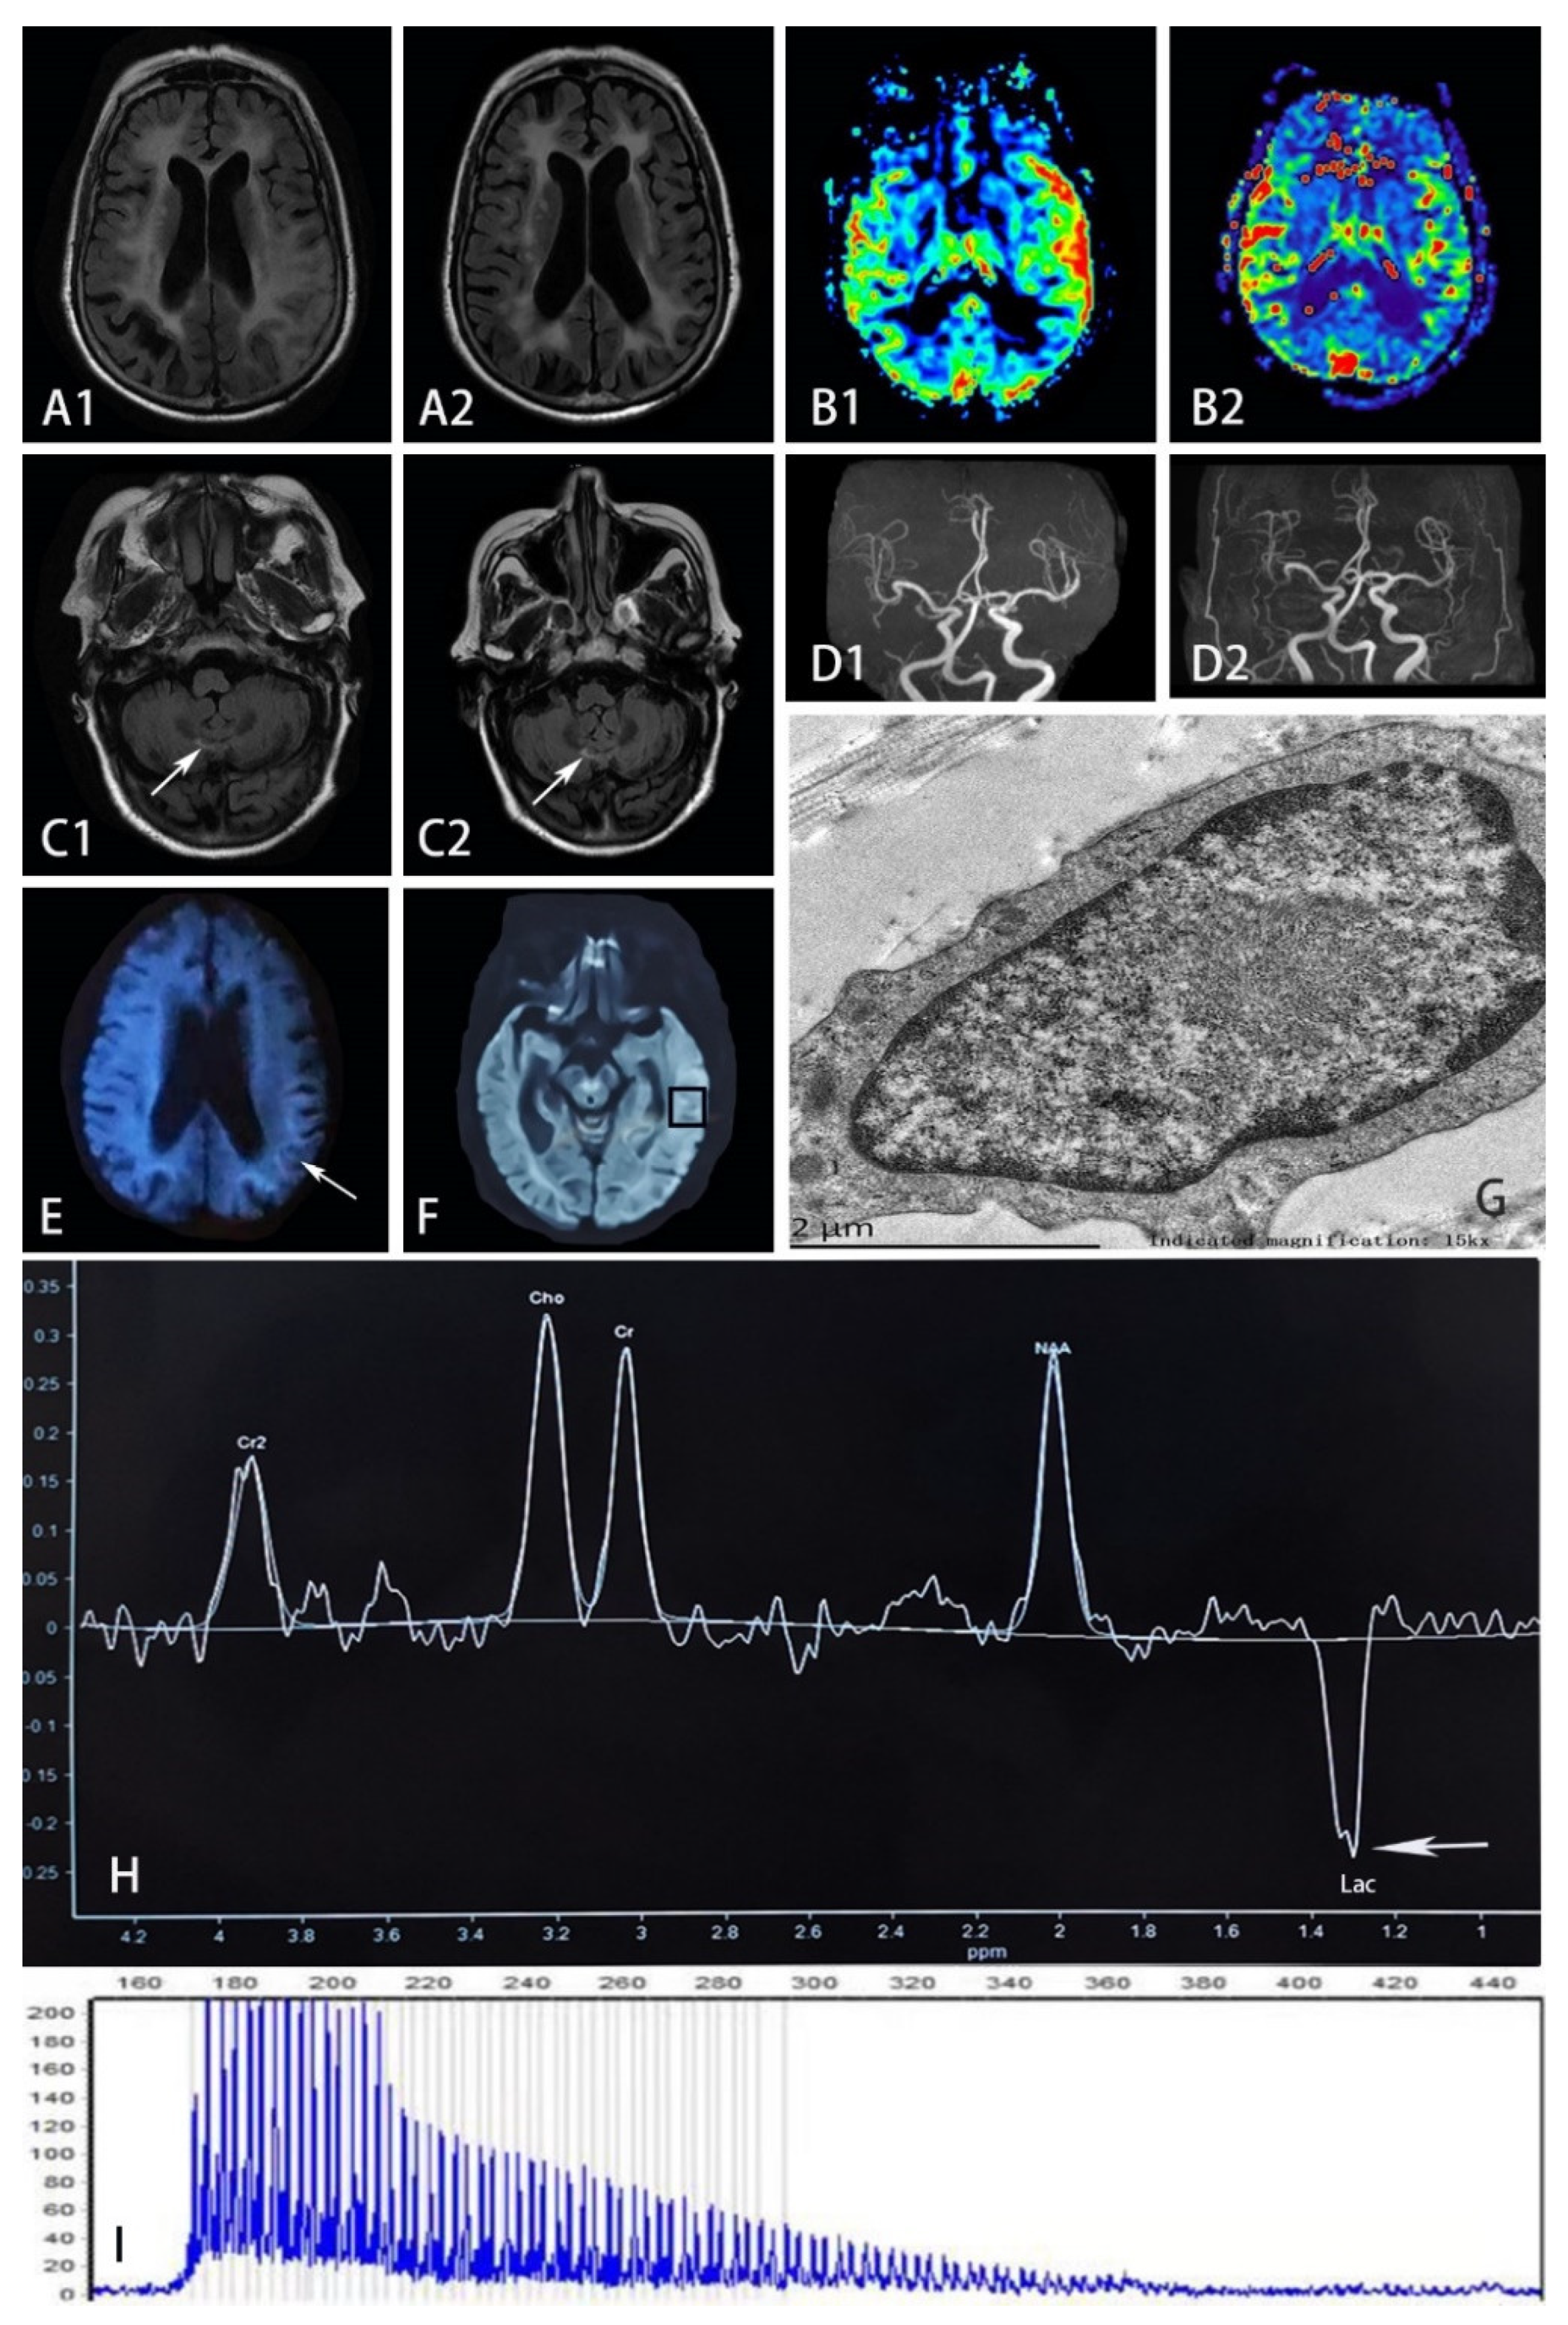

3. Results